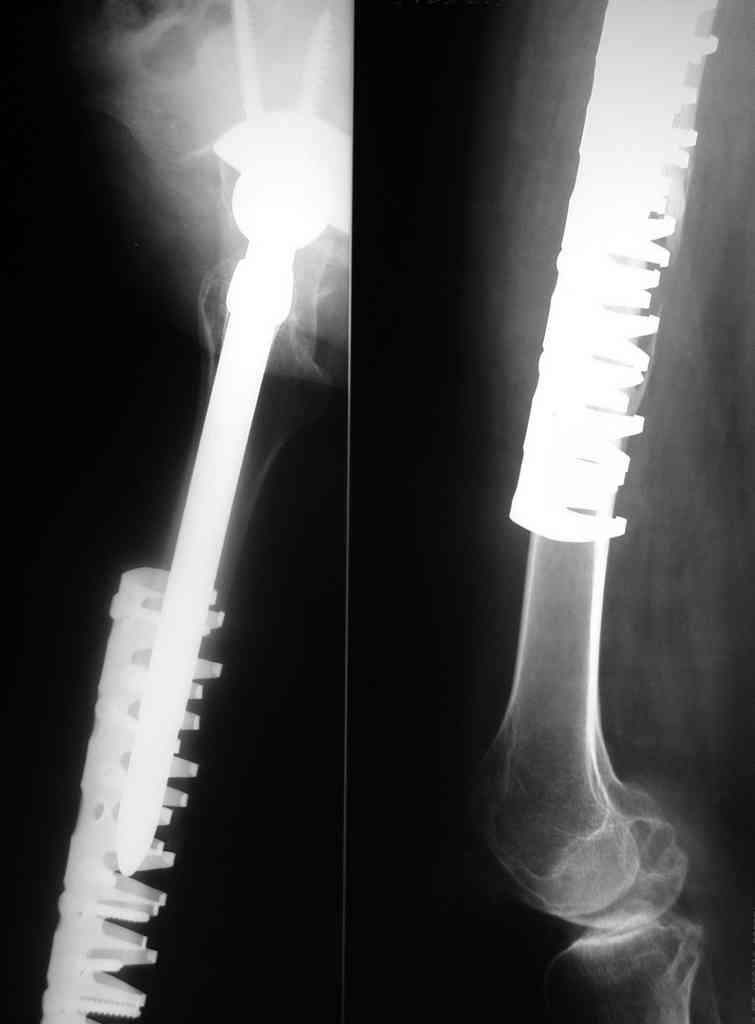

What do you think on advanced revision stem systems like the one?

Stems you show are fine but removing a well fixed AML stem means an extended trochanteric osteotomy, cutting the stem below its metaphyseal flair, then over reaming the distal piece of prosthesis. Can be done but is difficult, requires specialized equipment, and will create a lot of proximal bone loss and proximal femoral instability. Also, with the fracture, exposure of the hip joint is difficult because you can't rotate the hip by moving the lower leg. This means clamps on the proximal fragment further devascularizing the bone. You will be left with a bag of bone proximally using less than ideal distal fixation to encourage bone ingrowth to your revision prosthesis. Now you need ingrowth AND union.

I would still prefer leaving the well functioning total joint out of the procedure and making a better mechanical and biologic attempt on the

femur.

In German literature a lot of Authors says that in any case of periprosthetic fracture the energy of trauma causes a damage to the stability of the stem, so, in any case of B fracture is suggested a longer stem.

In our Institution we apply the Vancouver protocol with LCP as ORIF, but we realize that the healing of these fractures is quite long (6 months and

over) often in old patients. Perhaps the changing of the stem could be a faster way to help these patients.